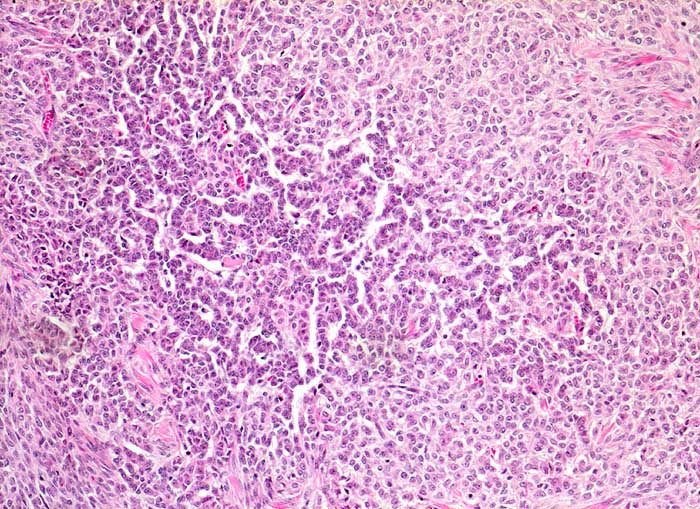

PathoPic ID 5332 - Granulosazelltumor vom adulten Typ des Ovars

Granulosazelltumor vom adulten Typ des Ovars

maligner Tumor

Ovar

Solides Tumorwachstum im Wechsel mit girlandenartigen schmalen Tumorzellsträngen.

Die Tumorzellen zeigen eine Positivität für Inhibin und CD99, sind jedoch negativ für EMA.

Ovarial-Tumor links -> Adnexektomie links. Frage: Dignität? CA125 im Normbereich.

Histologie

100